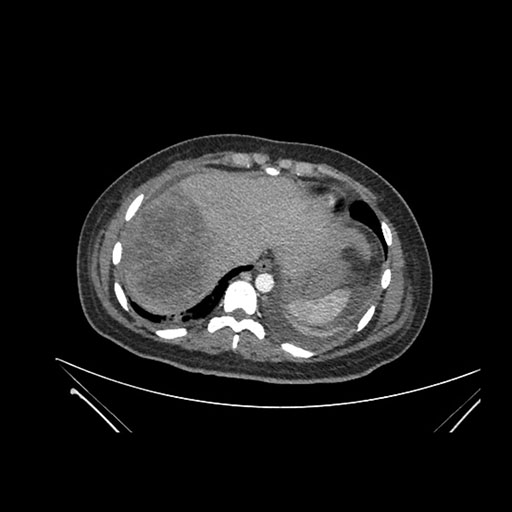

Imaging Analysis

Look through the patient's CT scan to identify any areas of concern for the necessary procedure.

Axial Arterial

Based on initial findings, which issue(s) would you be most concerned about?